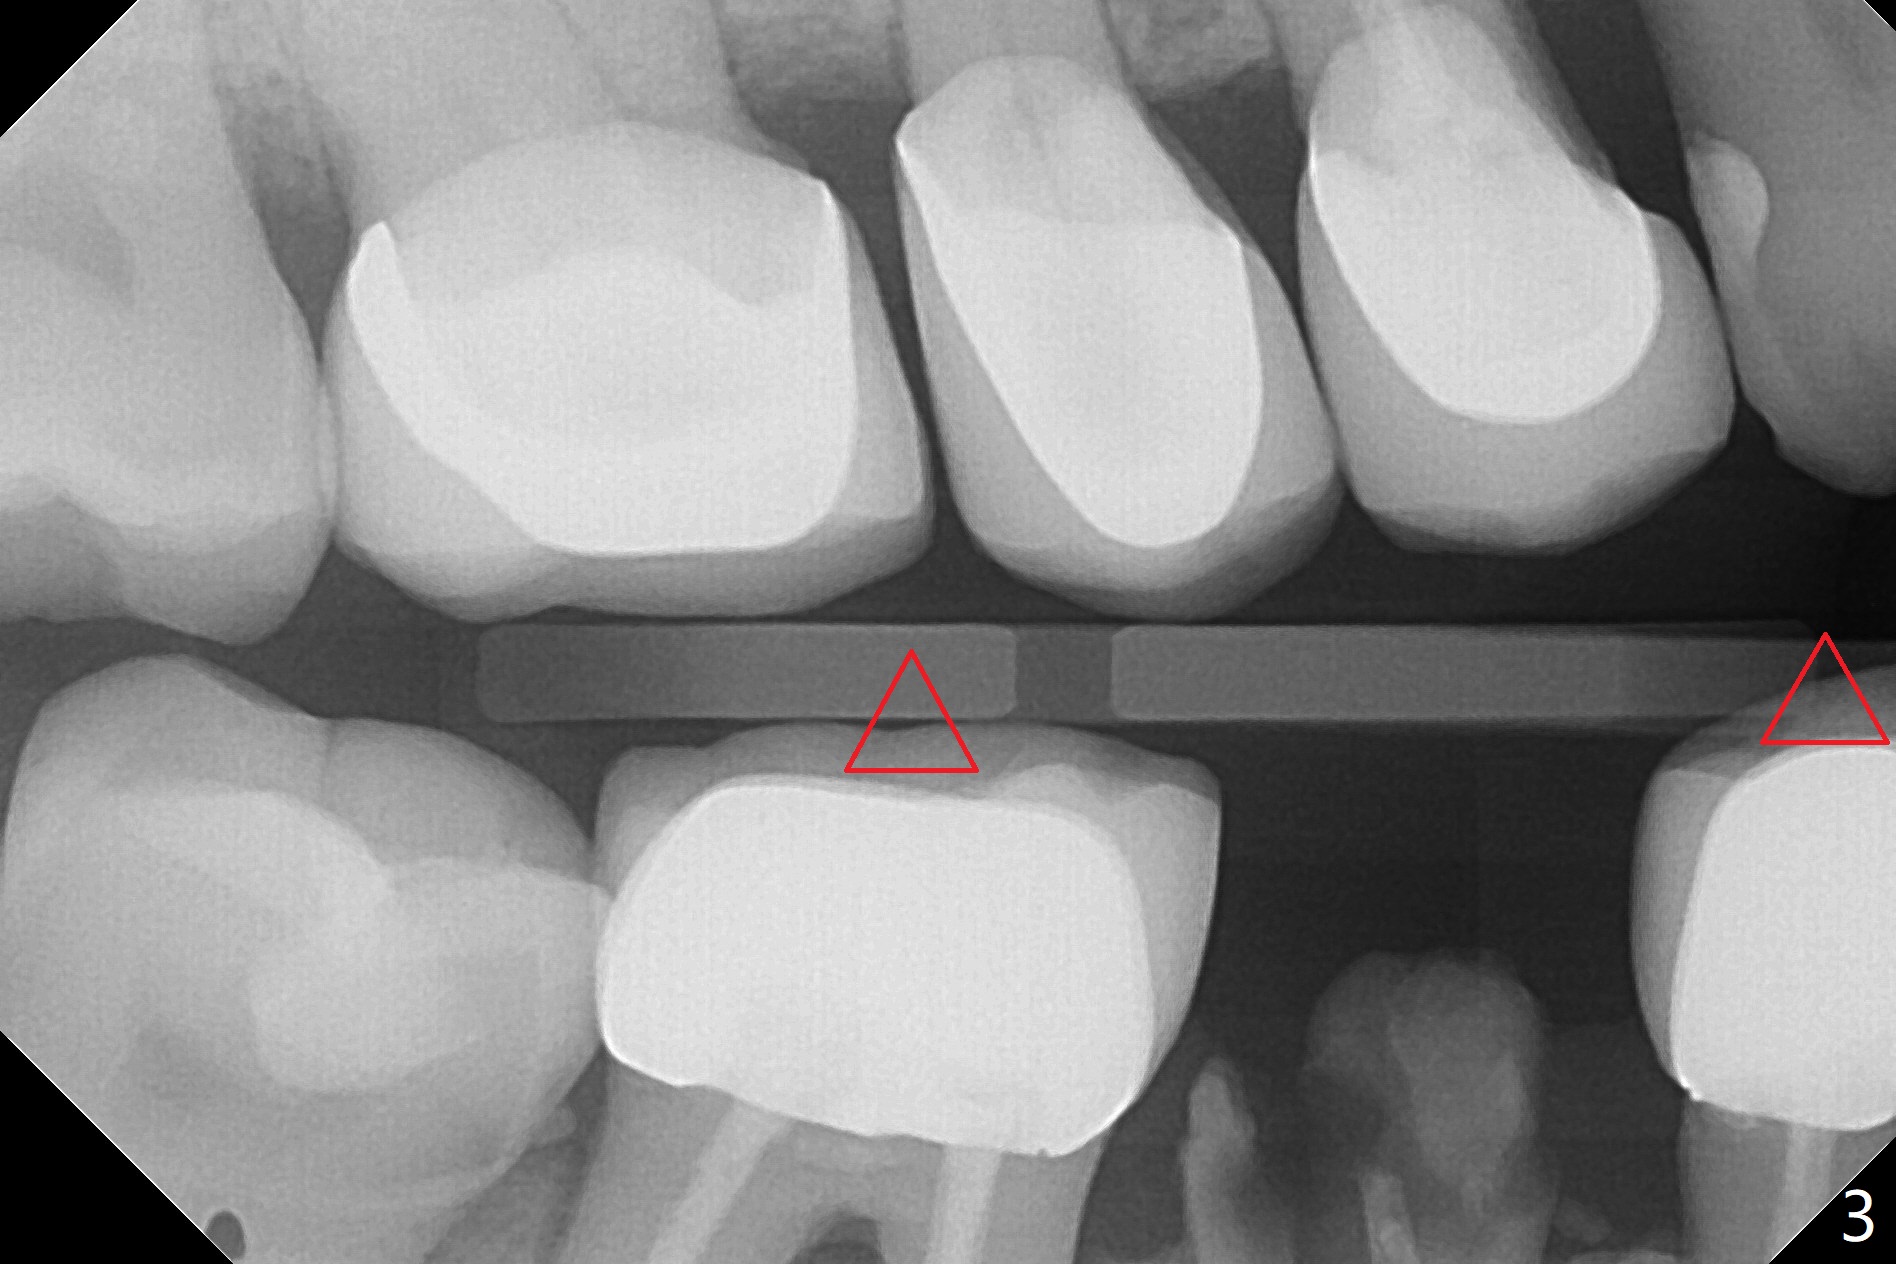

今天遇见一位特殊病人,54岁女,“右下一个牙齿断裂,我觉得一定要拔 (图一:5)。能不能同时种牙,减少痛苦。不过你是医生,一切由你决定”。为了炫耀,介绍导板,她还没有提钱的问题,估计必须再等十年才能碰见怎么有远见的土豪(夸张)。所以我们迫不及待拍摄CT,然后取模。至今有没有不对的地方,尤其是拍摄CT。要做导板周围(前后)有牙冠,在拍摄CT下,会产生折射(图二:*),影响CT精确度,不能与口内模型互相融合,从而影响导板精确度。如果实在想做导板,必须事先在牙冠上制作树脂cone(图三:红色三角形),然后拍摄CT和取模(或者scan),实验员才能准确融合两个图像。对于这个病例,只能做徒手种植,减少射线。不过增加手术时间,为了不损伤颏神经(图四),可能需要多次拍摄根尖片,增加无限的烦恼,一失足成千古恨。但是不会失去最后一个手段:PRF。